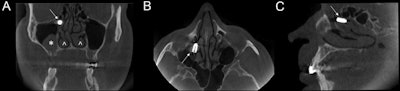

CBCT images in coronal (A), axial (B), and sagittal (C) sections show the implant located at the ethmoidal infundibulum level of the right maxillary sinus. The asterisk shows a mucus retention cyst in the right maxillary sinus. The arrowheads show the asymmetry of inferior turbinates, which  may be due to compensatory hypertrophy after the right septal deviation. Image courtesy of Filippo Cascio, MD, et al. Licensed under CC BY-NC 4.0.

CBCT images in coronal (A), axial (B), and sagittal (C) sections show the implant located at the ethmoidal infundibulum level of the right maxillary sinus. The asterisk shows a mucus retention cyst in the right maxillary sinus. The arrowheads show the asymmetry of inferior turbinates, which  may be due to compensatory hypertrophy after the right septal deviation. Image courtesy of Filippo Cascio, MD, et al. Licensed under CC BY-NC 4.0.The man was placed under general anesthesia and the implant was removed, they wrote. He reported no other symptoms after three days.